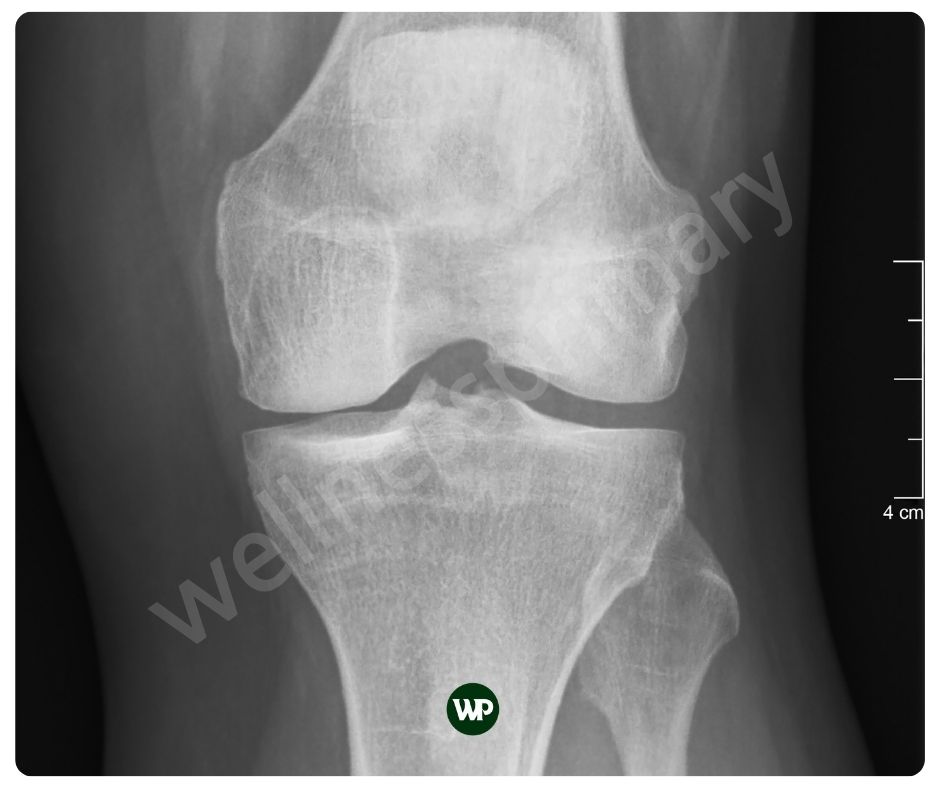

인간의 연골의 두께는 무릎의 대퇴골 연골의 경우 약 3mm에서 4mm 정도로 가장 두껍습니다. 어깨 관절 연골은 약 1mm~2mm에 불과하지요. 연골은 우리의 움직임을 위해 매우 중요한 역할을 하지만 실제로 매우 얇습니다. 그래서 가능한 빨리 연골 보호에 신경을 써야 합니다. 콘드로이친 효능은 연골의 손상을 예방하며, 이는 특히 연령 증가에 따른 연골 퇴화를 막는 데 중요한 역할을 합니다. 콘드로이친은 이미 손상된 연골의 경우, 그 회복을 돕고, 연골 세포의 재생을 촉진하는 매우 중요한 역할을 합니다.